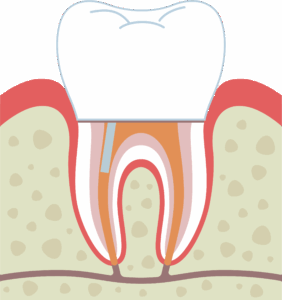

根管充填後、被せ物を装着

治療が終わった段階です。歯の根の先の方までしっかり詰め物をしています。